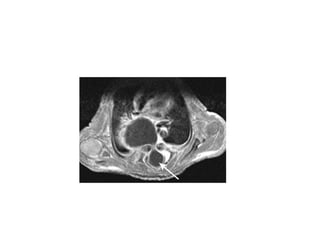

Beeld 172 De pijl staat bij de tip van de umbilicale arterielijn. A. Juist B. Onjuist C. Weet niet

Beeld 172 Depijl staat bij de tip van de umbilicale arterielijn. A. Juist B. Onjuist C. Weet niet